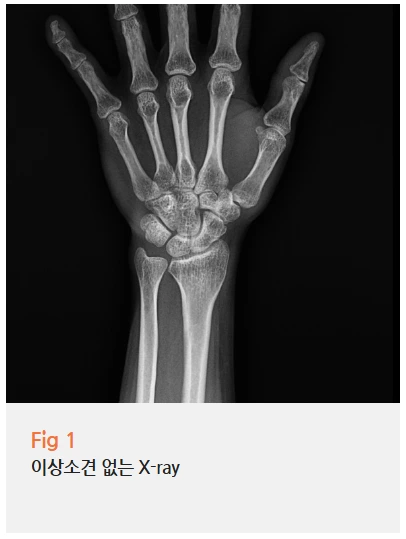

저는 우선 환자분의 상태를 정확히 파악하기 위해

X-ray 검사와 초음파 검사를 진행했습니다.

엑스레이는 다행히 정상으로 나왔는데,